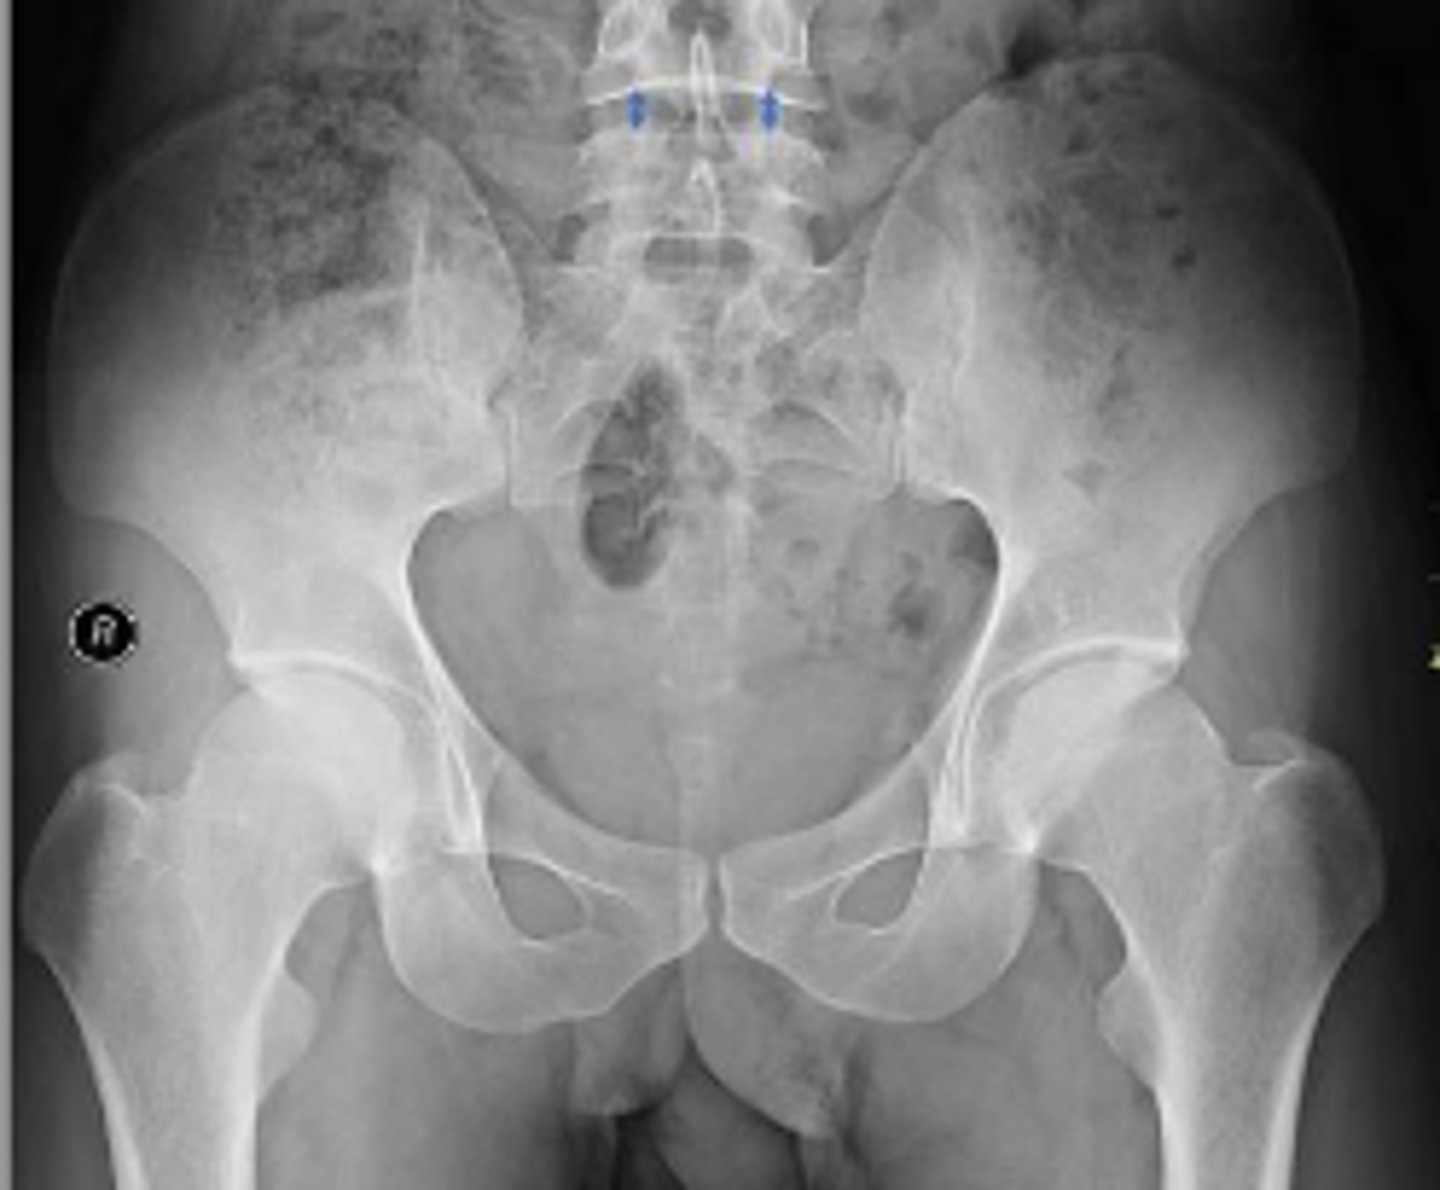

AP pelvis or bilateral hips

What is the name of the radiographic view?

PSIS

What are the arrows pointing to?

Right L5 transverse process

What is outlined?

Coccyx

L3/L4 IVD space

What IVD space is indicated by the arrows?